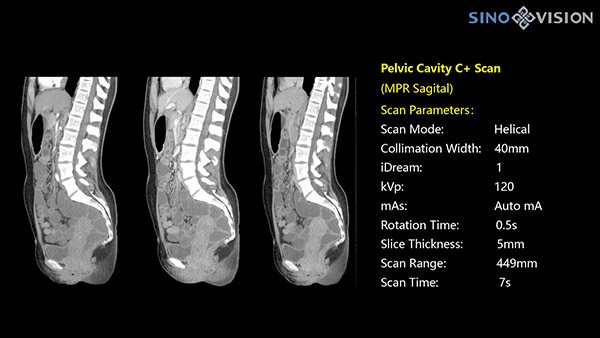

Инновационный 128-срезовый компьютерный томограф SinoVision InsitumCT 568 – это сочетание высокой скорости работы, низкой дозы и максимума возможностей для подавляющего большинства клинических случаев, как в рутинных, так и в углубленных специализированных исследованиях, в том числе педиатрические и кардиологические исследования при сверхнизких дозах.

РМК

Полнофункциональный 128-резовый компьютерный томограф InsitumCT 568 - это лучшее в новом поколении широкодиапазонных томографов с 128 срезами и большой диафрагмой. Этот КТ-сканер с большой апертурой обеспечивает 128 срезов КТ с диафрагмой 76 см, улучшает разрешение изображения до 21Lp/cm, помогает точно диагностировать и лечить заболевания, а также значительно улучшает клинические характеристики и расширяемость оборудования. Позволяет реализовать визуализацию в высоком разрешении и в малых дозах лучевой нагрузки.

Полнофункциональная платформа клинической диагностики может точно определять местонахождение и диагностировать общие повреждения качественно и количественно, а также достигать полнофункциональных клинических показателей, включая обширные кардиологические исследования со сверхнизкими дозами лучевой нагрузки.

- Динамическое сканирование